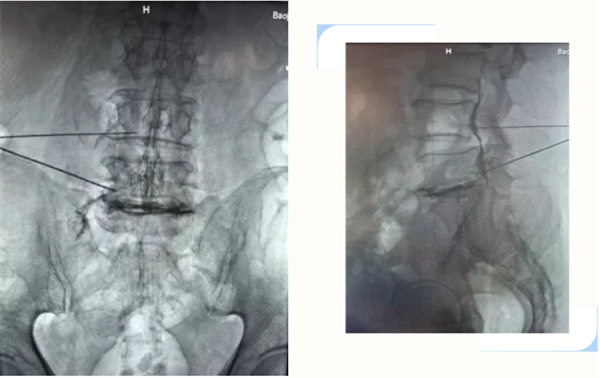

55歲的何師傅,反復腰背部疼痛不適,曾多次行保守治療,效果不理想,近3月來癥狀逐漸加重,伴有左臀部、左大腿疼痛,行走困難,遂就診我院骨四科,患者對常規手術非常恐懼。入院后,科主任楊永輝及團隊結合患者一般情況、癥狀、查體及影像學檢查,診斷為:腰椎間盤突出癥(L5-S1),綜合評估病情后,考慮到患者的訴求。為患者行L5-S1椎間盤突出膠原酶化學溶解+臭氧術。該技術無需開刀,僅需透視下“注射一針”,化學溶解突出、脫出的髓核,術后患者癥狀較前明顯好轉,可佩戴腰部固定支具下床活動。為同類患者提供新的選擇。

指將膠原酶及臭氧在C型臂引導下,精準注射到突出椎間盤內及周圍,一方面溶解并吸收突出椎間盤,另一方面抑制炎性因子滲出,促進組織修復,從而減輕神經根壓迫及炎性刺激,達到緩解疼痛、改善癥狀、提高生活質量的效果。